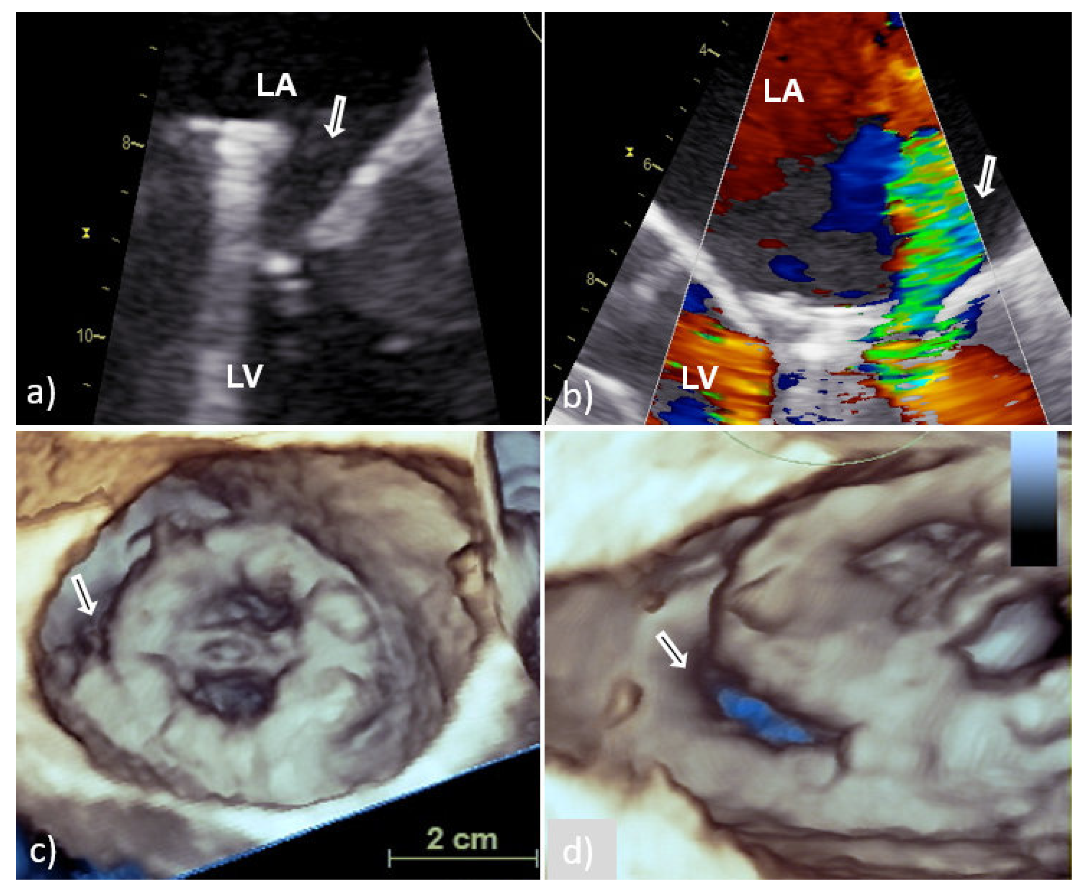

According to recent reports, 3D TEE provides clear, rapid, and detailed anatomical visualization of mechanical and bioprosthetic mitral valves in real time ensuring better assessment of mitral PVE-related complications and significant improvement in monitoring and preoperative surgical planning [9,10,11,12,13,14]. The surgeon’s view, which shows the mitral prosthesis with the aortic root at the 12 o’clock position, is identical to what the surgeon sees and is recommended as a standard orientation (Figure 1) [9,13]. Therefore, 3D TEE precise anatomical imaging of the mitral valve is better understood by cardiac surgeons [8]. An additional advantage of 3D TEE is better visualization of the mitral prosthesis from the left ventricle, although shading caused by a mechanical prosthesis can sometimes make its clear visualization difficult or impossible [8]. Finally, 3D TEE echocardiographic modality is capable of improving communication between members of the IE team.

It is obvious that by providing better images in comparison to 2D TEE, 3D TEE allows detailed anatomical visualization of PV and better characterization of vegetation allowing their differentiation from non-PVE changes such as thrombi, pannus, prosthetic sutures, mitral subvalvular tissue remnants (Figure 1d,e), and bioprosthesis leaflet degeneration [18]. Since these findings have a very similar echocardiographic appearance, sometimes it is not possible to distinguish them from each other only by echocardiographic parameters.

Figure 1. Transesophageal echocardiography of MVP: Presentation of the MVP in different two-dimensional planes needs careful mental reconstruction to translate the echo description into the anatomy (ac); 3D TEE reconstruction allows realistic anatomic image of the MVP similar to the one the surgeon sees from the LA (surgeon’s view) (d); cropped and enlarged 3D TEE image allows better presentation of the MVP and surrounding structures (white arrow—residual tissue of posterior leaflet of native mitral valve) (e); schematic presentation of surgeon’s view (clockwise orientation) with AV anteriorly at 12 o’clock position, IAS at the middle 3 o’clock position, and LAA at the lateral 9 o’clock position (f). AV—aortic valve; IAS—interatrial septum; LA—left atrium; LAA- left atrium appendage; LV—left ventricle; MVP—mitral valve prosthesis; and 3D TEE—three-dimensional echocardiography.